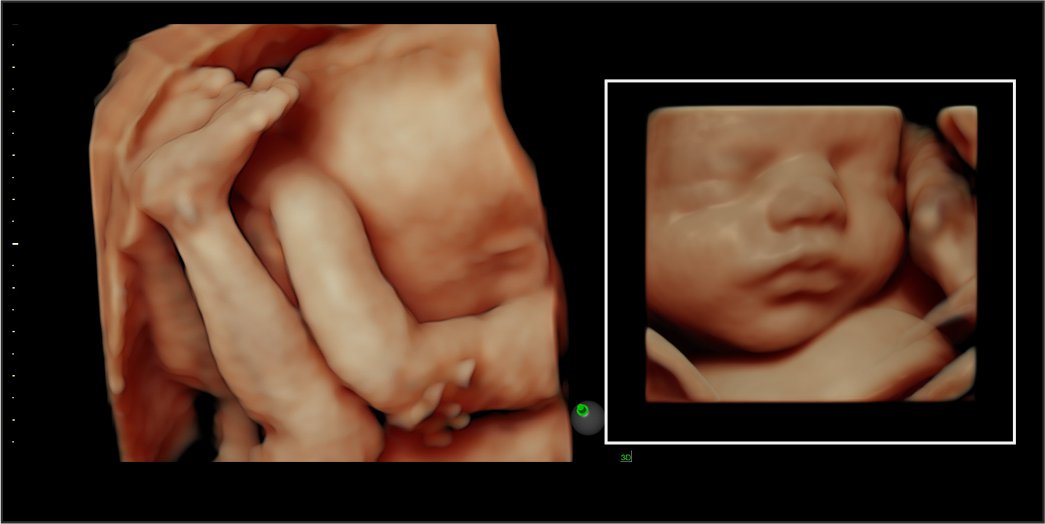

A 4-D ultrasound may also be called a dynamic 3-D ultrasound. Unlike other ultrasounds, a 4-D ultrasound creates a moving video of the fetus. It creates a better image of the baby’s face and movements. It also captures highlights and shadows better. This ultrasound is performed similarly to other ultrasounds, but with special equipment.